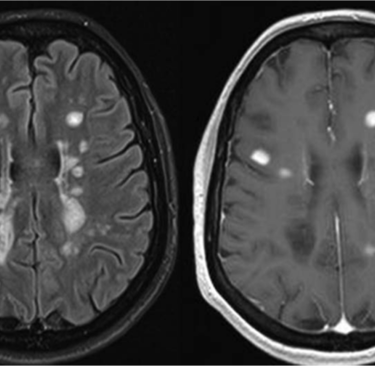

El diagnóstico se basa en una combinación de historia clínica, exploración neurológica y pruebas complementarias como resonancia magnética cerebral y medular, análisis de líquido cefalorraquídeo o estudios neurofisiológicos. Cada una de estas pruebas ayuda a confirmar la presencia de lesiones típicas de esclerosis múltiple y a diferenciarla de otras patologías. En la consulta de neurología de Burriana, ofrecemos una orientación experta para solicitar las pruebas necesarias y dar sentido a los resultados obtenidos.